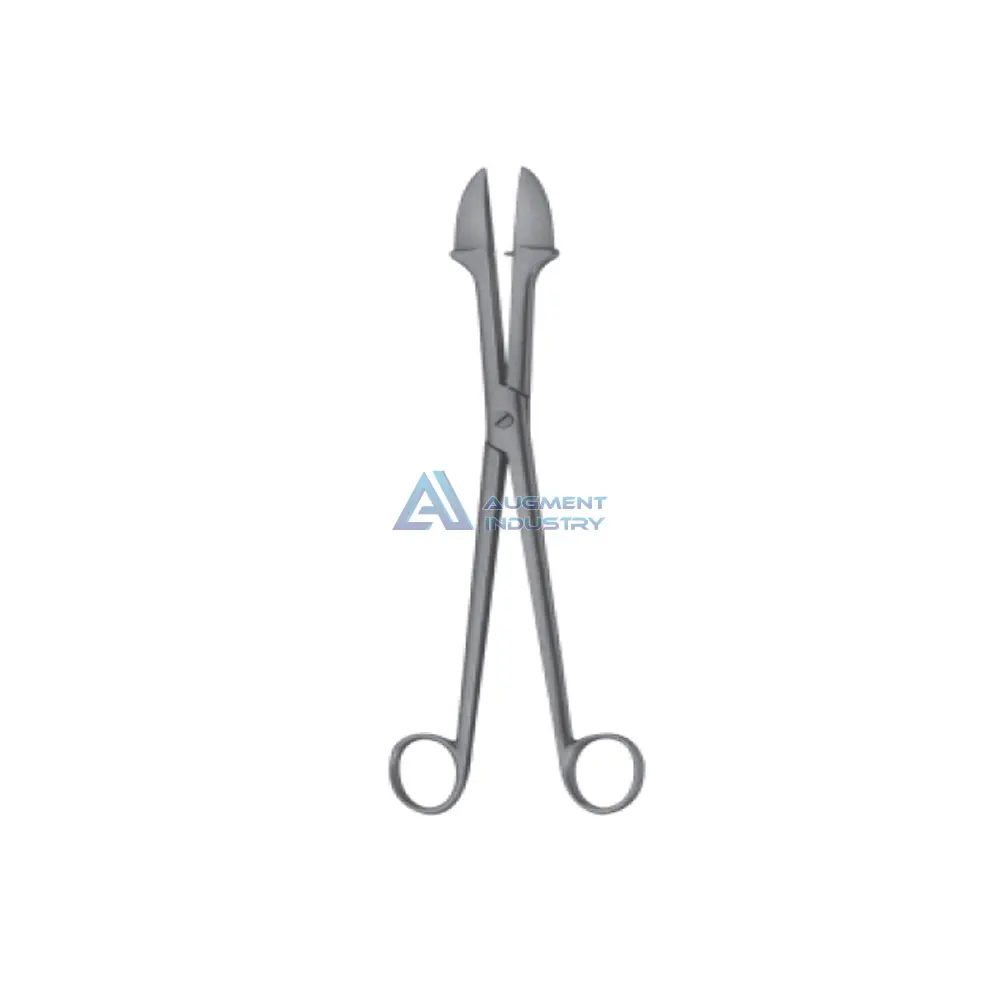

SMELLIE Perforator 270MM Stainless Steel Surgical Instruments Obstetrics Placenta and Ovum Forceps

- Category:

- Supplier: AUGMENT,INDUSTRY

In Stock